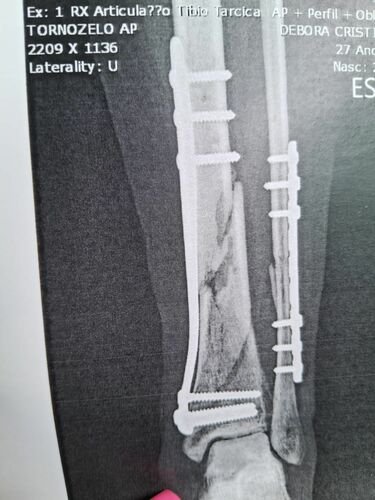

Sou a Jaqueline, criei essa vaquinha para arrecadar dinheiro para cirurgia da minha irmã Debora Cristina Luebke, que sofreu um acidente de moto no dia 07 de março de 2024. Desde então já passou por três cirurgias, e ainda não se recuperou. Medico nos informou que ela precisara passar por uma quarta cirurgia, que seria um tratamento cirúrgico pseudoartrose tíbia (A pseudoartrose é uma complicação que ocorre quando o osso não se consolida após uma fratura.) porem o valor ficou de R$ 19.710,00. A cirurgia seria com um enxerto sintético para colocar na tíbia e, seria menos invasiva e não deixaria com sequelas, com recuperação de 3 meses. Se formos esperar para fazer pelo SUS, seria feito outro tipo de cirurgia, no qual ela precisaria tirar um osso do corpo dela e colocar na tíbia e, ainda assim, ela poderia ficar com sequelas, ficando com uma perna maior que a outra, tendo que colocar a parabolica e sem previsão de quando o osso irá calcificar. Se isso acontecer, o trabalho dela que hoje em dia é de vigilante, ela não poderá mais atuar. Por isso venho por meio dessa vaquinha, pedir a ajuda de todos, qualquer valor é bem-vindo! Temos 30 dias para arrecadar esse valor estamos correndo contra o tempo. Conta no nome de Jaqueline CHAVE PIX EMAIL: deboracristinaluebke@gmail.com